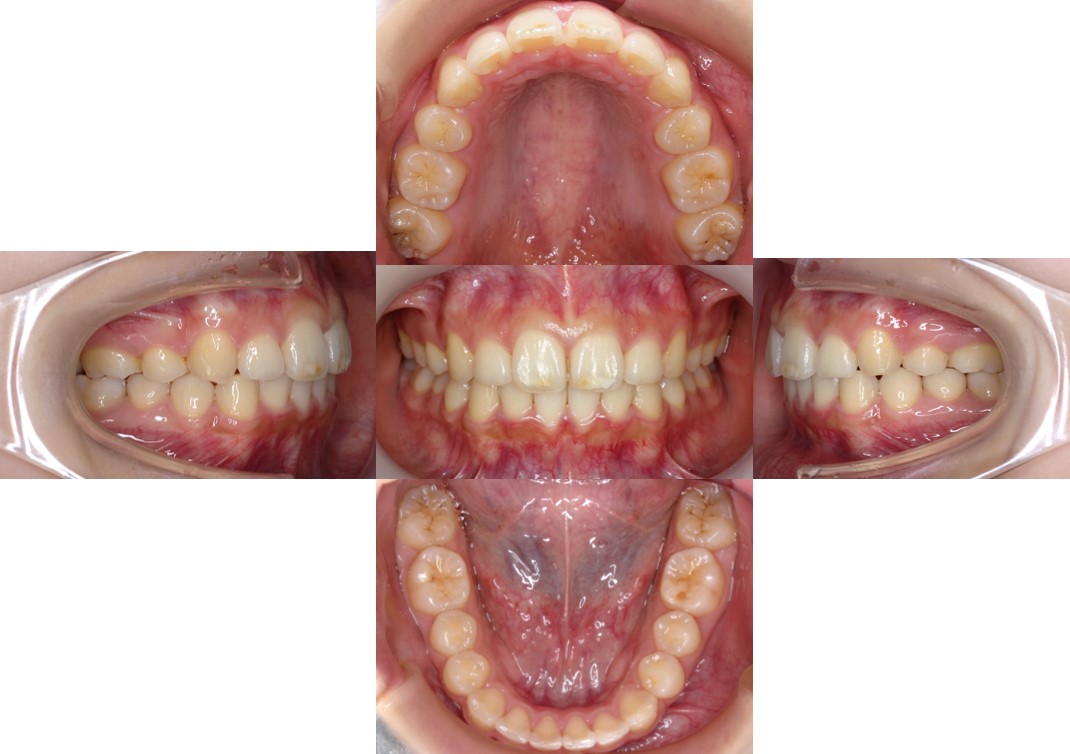

後戻りしていた前歯が収まって上下の歯がしっかり噛むようになりました。

今後は後戻り防止のために経過観察とリテーナーの装着を頑張りましょう!

| 治療費用 | 検査・診断:税込38,500円/裏側矯正治療(リンガル矯正):税込1,397,000円 |

| 治療期間 | 約2年2カ月(29回) |

| 抜歯 | 有(上顎両側4番) |

| 矯正の装置 | 裏側矯正(舌側矯正) |